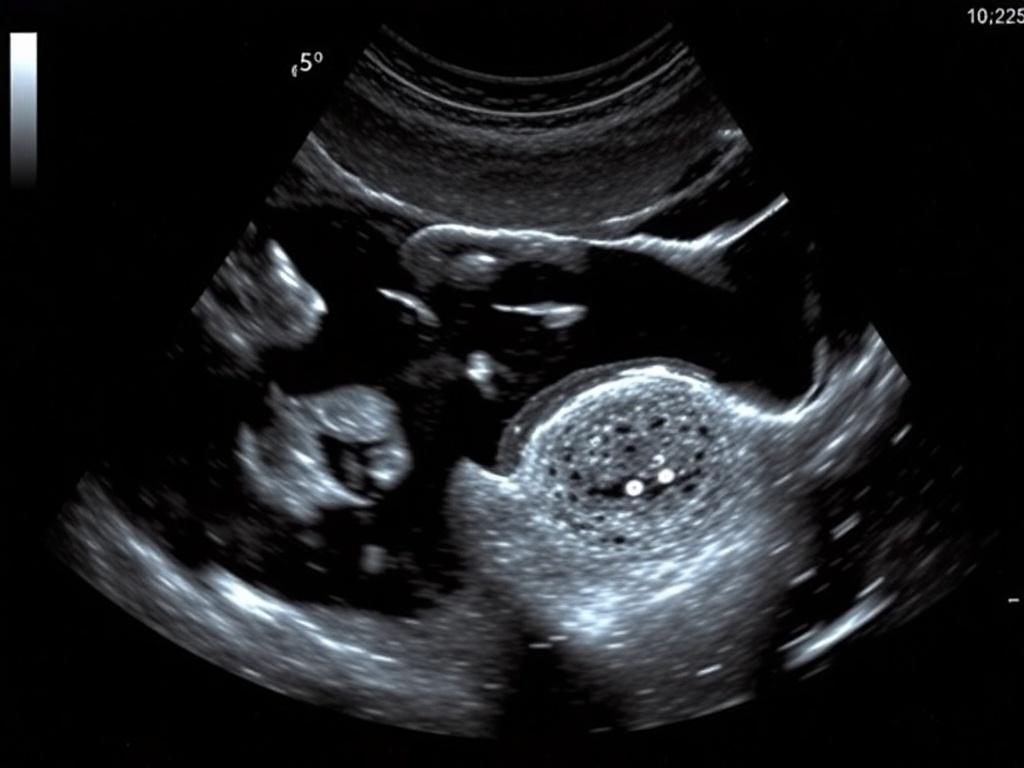

Ультразвуковое исследование использует звуковые волны для визуализации органов малого таза. На экране врач видит форму матки, толщину слизистой оболочки, структуру миометрия и состояние яичников. Исследование бывает двух основных видов: трансабдоминальное (через брюшную стенку) и трансвагинальное (через влагалище). Первый — более общий, второй даёт детальную картину, особенно для яичников и эндометрия. Больше информации о том какая на УЗИ матки и яичников цена, можно узнать пройдя по ссылке.

Трансвагинальное УЗИ выполняют специальным датчиком, который вводят во влагалище. Это не больно — скорее неприятное ощущение для тех, кто волнуется. Трансабдоминальное проводят с покрытым датчиком по коже живота, и для хорошего изображения обычно нужен полный мочевой пузырь.

В кабинете вас попросят расположиться на гинекологическом кресле. При трансабдоминальном варианте специалист нанесёт гель на живот и проведёт датчиком по поверхности кожи. В трансвагинальной версии датчик покрывают одноразовым чехлом и смазывают гелем для удобства введения. Сканирование занимает обычно 10–20 минут, иногда до получаса, если требуется более детальное исследование или допплер-контроль кровотока.

В ходе исследования врач может попросить слегка повернуться или изменить положение. Если чувствуете дискомфорт или напряжение, скажите об этом — исследователь постарается быть аккуратным и объяснить каждый шаг. В конце вы получите заключение — устное и письменное, иногда с распечатанными изображениями.

- Эндометриома. Киста, ассоциированная с эндометриозом; имеет характерный «шоколадный» вид на УЗИ и требует планирования лечения.

- Синдром поликистозных яичников. На УЗИ видно много мелких фолликулов и увеличенный объём яичников; диагноз ставят на основании комплекса симптомов и анализов.